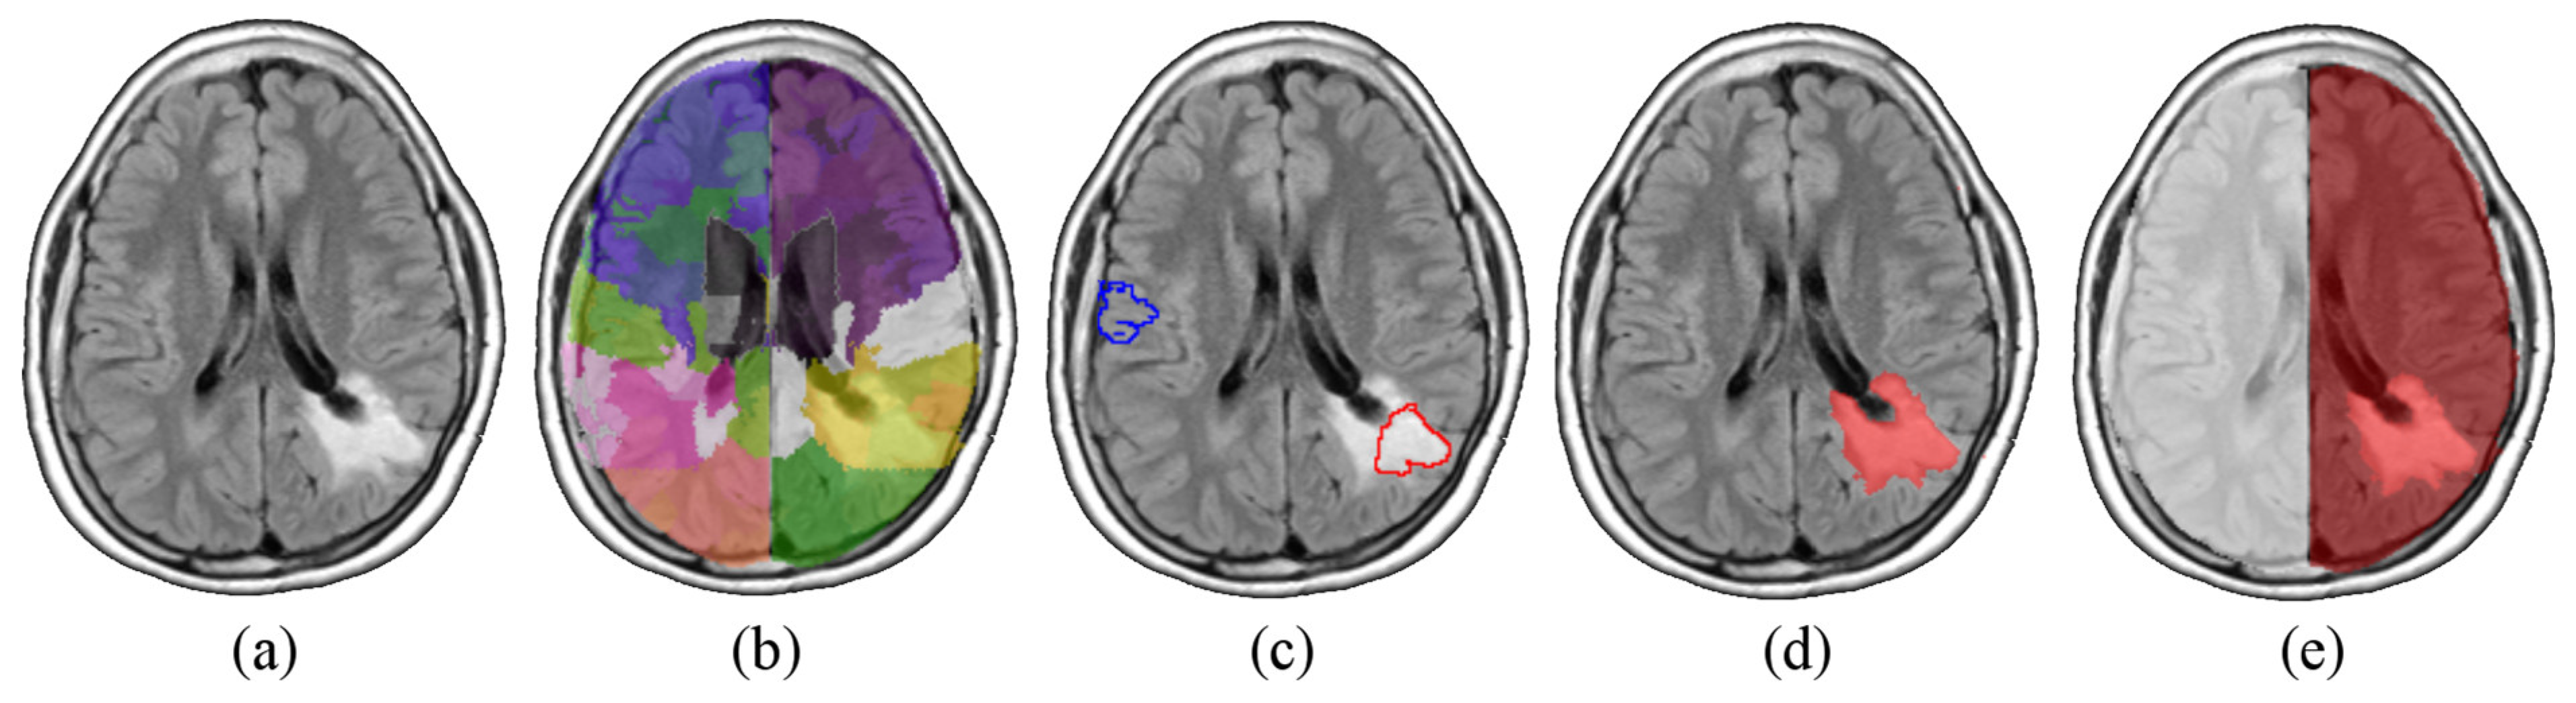

The final mask Mn was then computed by averaging the five Mi. In the end, each PET P was provided with a mask Mn containing the normal, reference, tissue. An infographic of the workflow, for the extraction of Mn, is summarized in Figure S2a (Supplementary Materials). Each mask Mn was usually a large, connected area consisting of non-affected tissue. Its intensity characteristics showed a mono-modal distribution, which is coherent with the removal of districts showing significantly different uptake (Supplementary Materials, Figure S2b). The arithmetic mean cn of the intensities in Mn was chosen to be the representative of the normal tissue. Finally, the normalized image Pn was obtained dividing the intensity of each voxel of P by cn. An analogous procedure was carried out to normalize P to the activity of the normal striatum. Briefly, the uptake of the striatum in [18F]F-DOPA scans allowed the Y-filter to operate a coarse segmentation of subcortical structures. Knowing the position of the striata from the spatial normalization to MNI coordinates, we could outline a volume Ms containing points discarded from Y which in turn contained the whole striatum located in the non-affected hemisphere. From Ms a representative value of the striatal activity cs was extracted. In Figure 2, the steps leading to the definition of Ms are summarized. Target PET P voxels were then divided by cs, and the resulting Ps is the PET scannormalized to the mean activity of the normal striatum.

Figure 2.

Diagram showing the processing that leads to the definition of Ms. By integrating the information on the position of the basal ganglia (retrieved from the normalization to the MNI coordinates, purple area within the purple box) with the mask Mn obtained with the Y-filter (green region), it is possible to delineate a volume Ms that contains the whole striatum (yellow area).